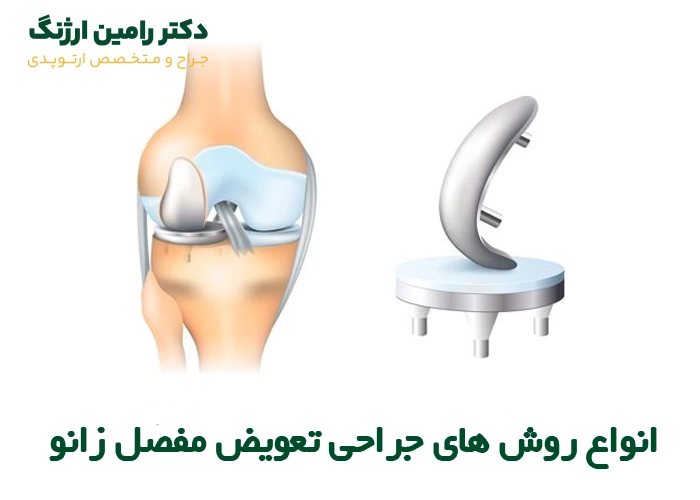

انواع روش های تعویض مفصل زانو

جراحی تعویض مفصل زانو بسته به میزان آسیب مفصل و نیاز بیمار، روشهای مختلفی دارد. در ادامه، مهمترین روشها را معرفی میکنیم:

۱. تعویض کامل مفصل زانو (Total Knee Replacement)

در این روش، تمام سطوح مفصل شامل انتهای استخوان ران، بخش فوقانی استخوان ساق و در صورت نیاز سطح پشتی کشکک با قطعات مصنوعی جایگزین میشود. این نوع جراحی برای بیمارانی انجام میشود که تمام بخشهای مفصل آنها دچار فرسودگی و درد شدید شده است.

۲. تعویض جزئی مفصل زانو (Partial Knee Replacement)

گاهی تخریب مفصل فقط در یکی از بخشهای داخلی یا خارجی زانو اتفاق میافتد. در این حالت، فقط همان قسمت آسیبدیده با پروتز جایگزین میشود. یعنی در این روش جراح برش کوچکتری روی زانو ایجاد میکند؛ دوران نقاهت کمتر شده و فرد سریعتر به زندگی برمیگردد و همچنین بعد از عمل درد کمتری را تجربه خواهد کرد.

۳. تعویض مفصل زانو با روش کم تهاجمی (Minimally Invasive)

در روش کمتهاجمی که از روشهای جدیدتر محسوب میشود، جراح با ایجاد برشهای کوچک، باعث میشود آسیبی به بافتهای اطراف مفصل نرسد یا حداقل آسیب برسد. به همین دلیل، بیمار درد و ورم کمتری را تجربه کرده و زودتر به حرکت طبیعی باز خواهد گشت.